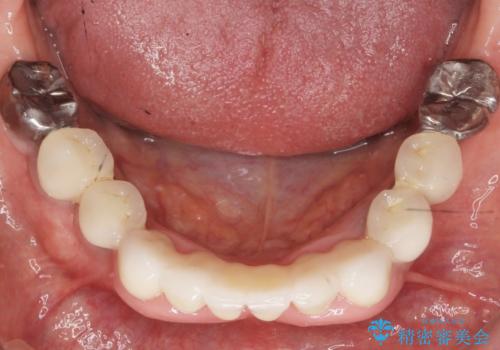

抜歯後歯肉の治癒を十分に待ったのち、ブリッジによる補綴治療を行いました。

- ¥1,010,000 (仮歯×9本、ファイバーコア×1本、ジルコニアクラウン スタンダード×9本)費用は治療当時の料金となります

自然な仕上がりと使い心地に喜んで頂けました。

奥歯の治療もやりたいとおっしゃって下さり、今後進めていく予定です。

ジルコニアクラウン スタンダード